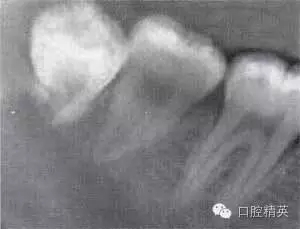

圖6-4 以上類型的下頜第三磨牙由于根阻力大,一般需要分根才能拔除

A.多根牙 B。超長根 C。牙根向遠中彎曲 D。兩根環(huán)抱 E。根分叉大 F,根端肥大 G。彎根 H.U型根(X線片及離體牙)